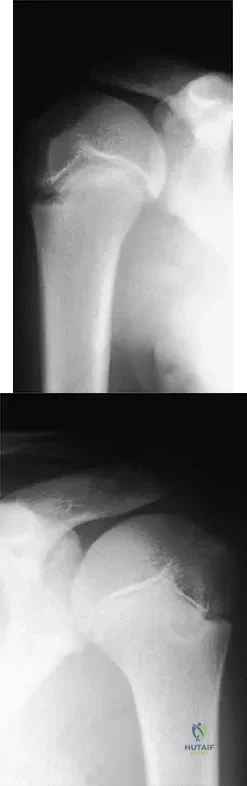

A right-handed 14-year-old pitcher has had a 3-month history of shoulder pain while pitching. Examination reveals full range of motion, a mildly positive impingement sign, pain with rotational movement, and no instability. Plain AP radiographs of both shoulders are shown in Figures 25a and 25b. Management should consist of